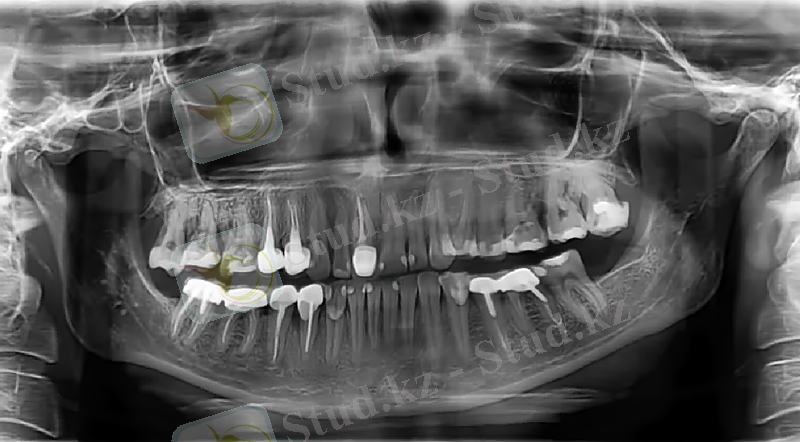

Тақырыбы: Тістер мен жақ сүйектерінің жасқа байланысты рентгендік көріністерінің ерекшеліктері (жас шақта, қарт адамдарда, инволюциялық)

В) Жақ сүйектерінің рентгендік көрінісі